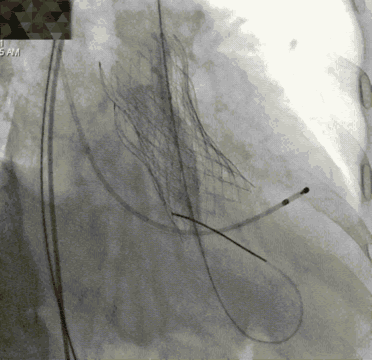

降主血管迂曲,弓部夹角锐利,弓部宽度较短,可谓是“山路十八弯”,得益于TaurusOne®输送系统优异的过弓性能,并在Snare辅助下顺利完成瓣膜系统过弓。

对于单纯返流患者来说,术前也分析了瓣膜移位的风险比较高。结合术前的分析与术中的情况,为保证患者的治疗效果,术中进行了“瓣中瓣”的策略,即第一个瓣膜在非稳定状态下作为锚定骨架,便于第二个瓣膜顺利植入并重建血流动力学。

平行导丝技术第二个瓣膜过弓

第二个瓣膜释放过程